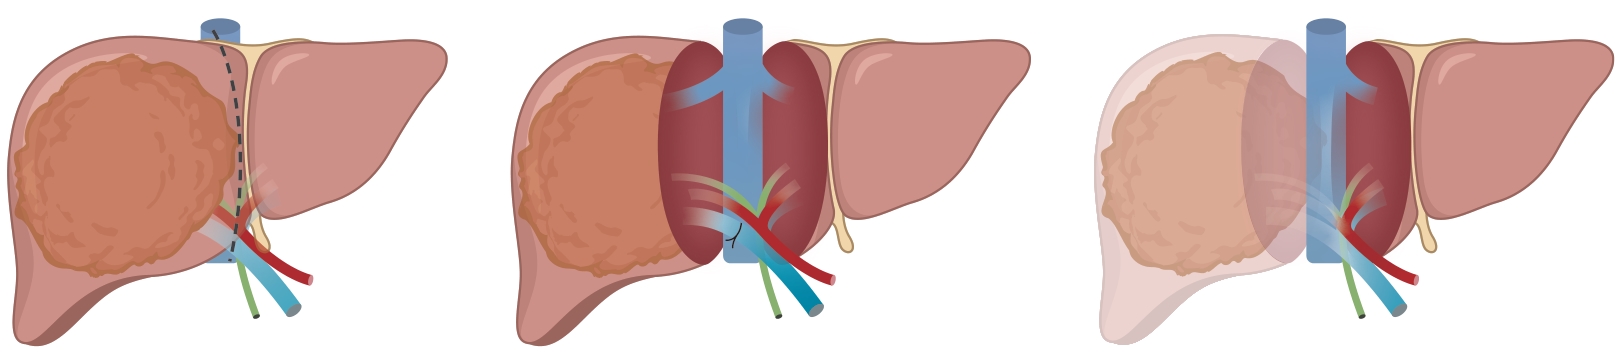

联合肝脏分隔和门静脉结扎的二步肝切除术(ALPPS)与肝癌

周俭, 王征

2025, 41(8): 1487-1490. DOI: 10.12449/JCH250802

摘要(698) HTML (216) PDF (1720KB)(95)

摘要:

联合肝脏分隔和门静脉结扎的二步肝切除术(ALPPS)是肝脏外科突破性的创新技术,提高了Ⅰ期无法手术切除巨大/多发肝癌的手术切除率。ALPPS手术方式的不断改进,进一步提高了手术的安全性。与系统治疗、局部治疗导致的肿瘤学转化相比,在手术切除成功率、间隔时间方面,ALPPS具有显著优势。未来研究应重点关注ALPPS术后患者的长期肿瘤学预后和生活质量评估。